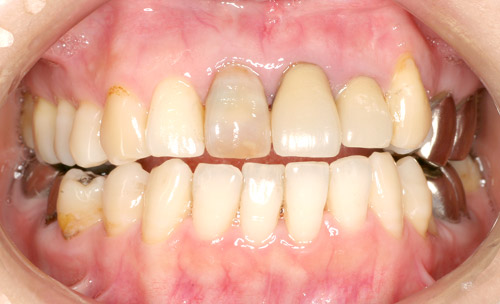

ダイレクトボンディング術前

ダイレクトボンディング術後

オールセラミック術後&ダイレクトボンディング術前

オールセラミック術後およびダイレクトボンディング術後